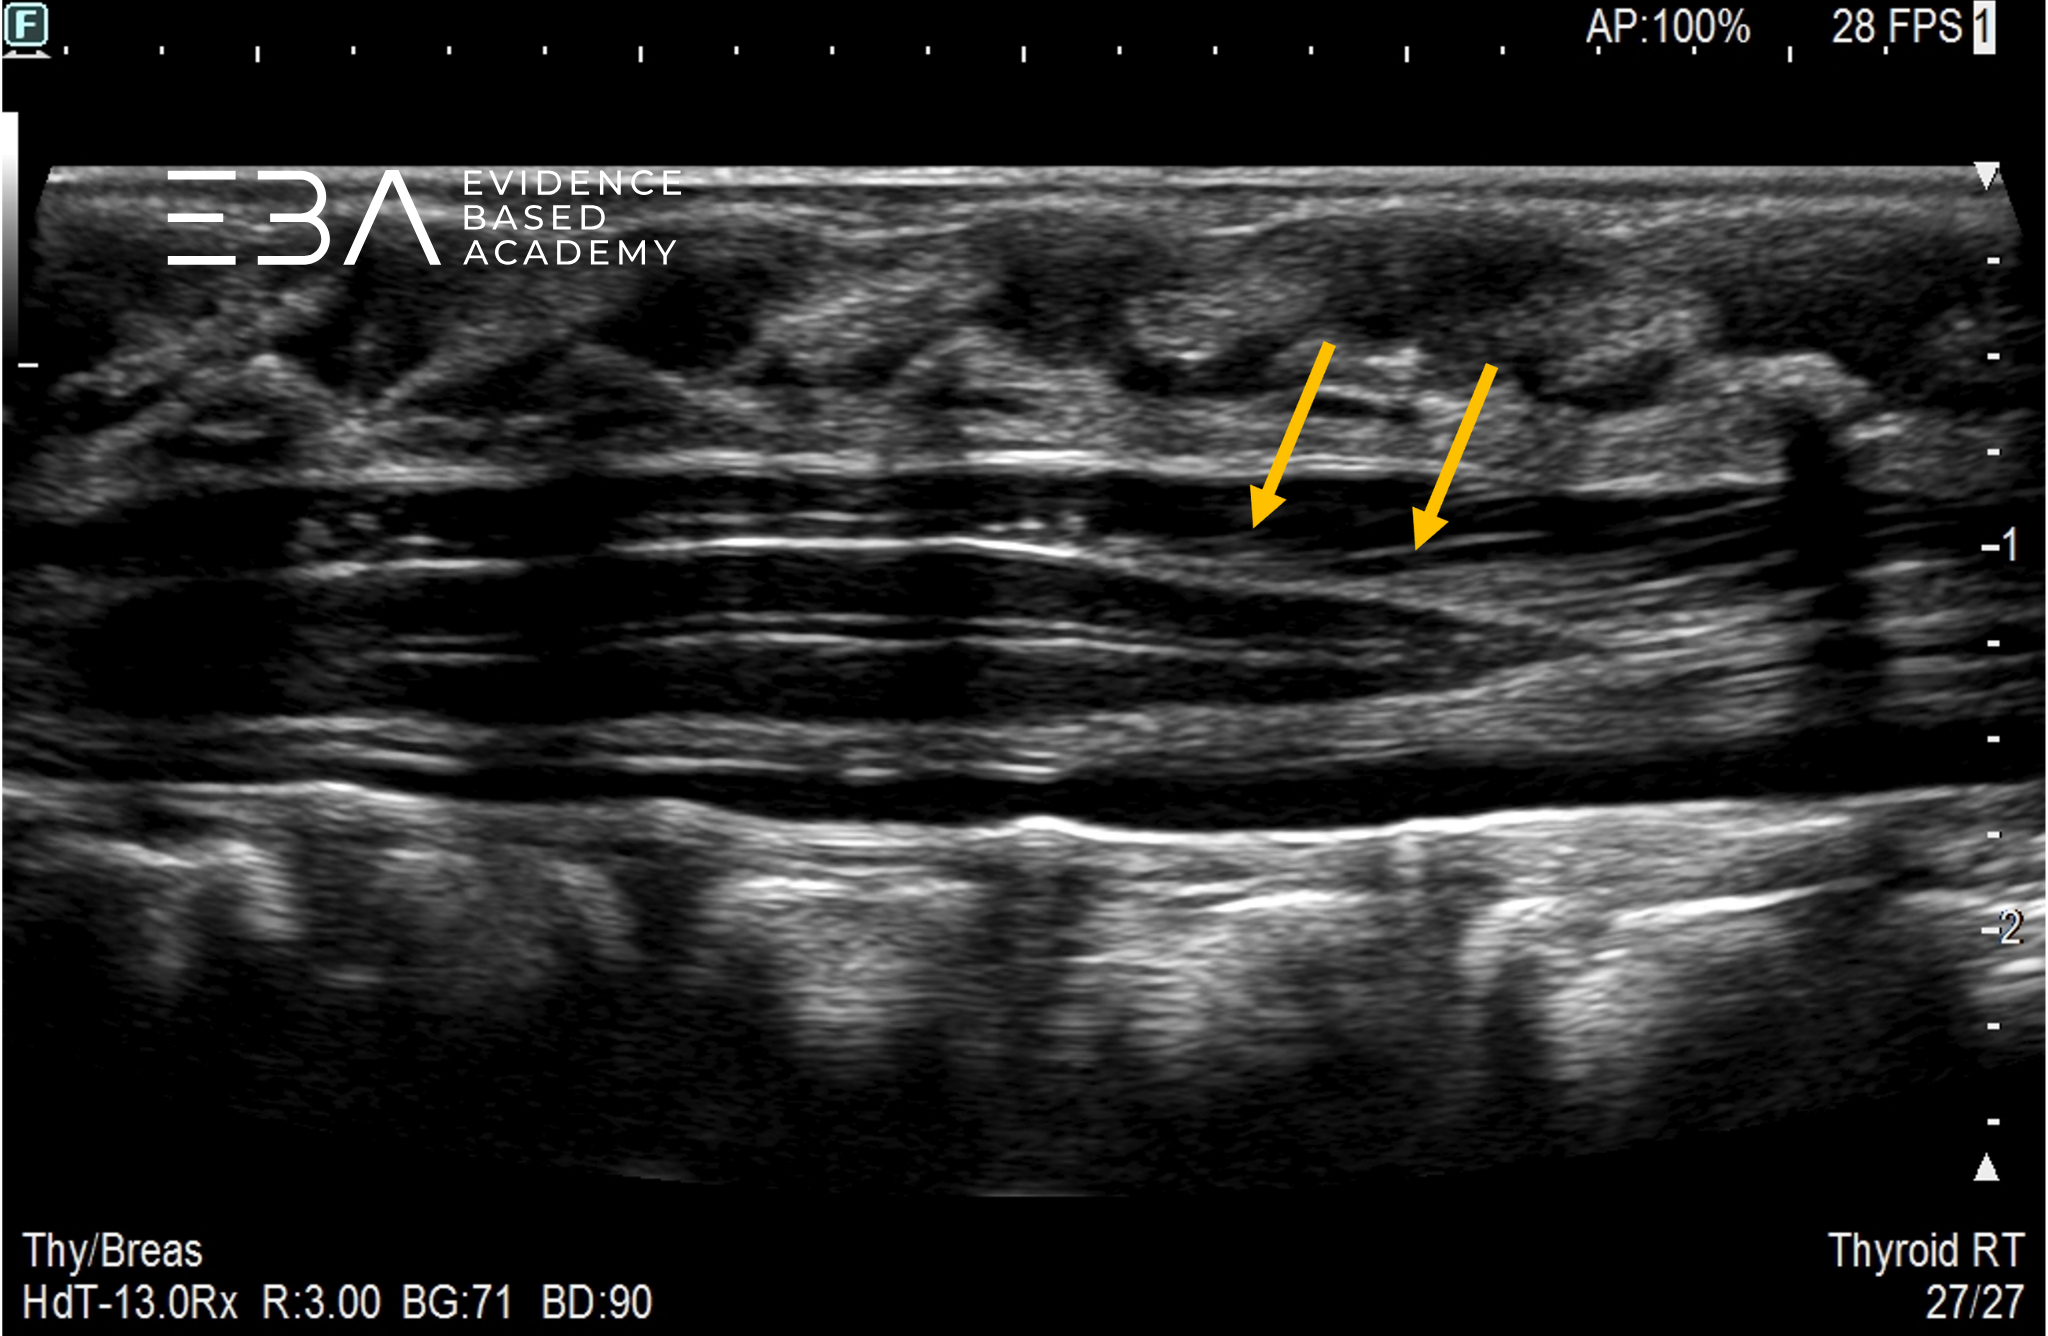

fot. 5

Kanał kręgowy, przekrój podłużny odcinka krzyżowego. Niebieską strzałką zaznaczono stożek rdzenia kręgowego, pomarańczową strzałką włókna ogona końskiego.

fot. 16

Kanał kręgowy, przekrój podłużny odcinka lędźwiowego i krzyżowego. Niebieską strzałką zaznaczono koniec stożka rdzenia kręgowego, pomarańczową strzałką zaznaczono włókna ogona końskiego.

Nić końcowa jest pasmem włóknistym rozciągającym się od stożka rdzenia do ogonowego końca kanału kręgowego, otoczonym nerwami ogona końskiego. Dystalnie od stożka rdzenia widocznych jest kilka echogenicznych linii odpowiadających nici końcowej i korzeniom nerwowym ogona końskiego.

Prawidłowa grubość nici końcowej wynosi poniżej 2 mm na poziomie L5-S1. Dokładniej, nić prawidłowa nić końcowa ma średnicę od 0,5 do 2,0 mm.

Pogrubiała nić końcowa wykazuje zwiększoną echogeniczność w porównaniu z sąsiadującymi korzeniami nerwowymi ze względu na niewielką objętość odkładającej się w niej tkanki tłuszczowej. Może to być uznane za wariant prawidłowy, jeśli grubość wynosi poniżej 2 mm.